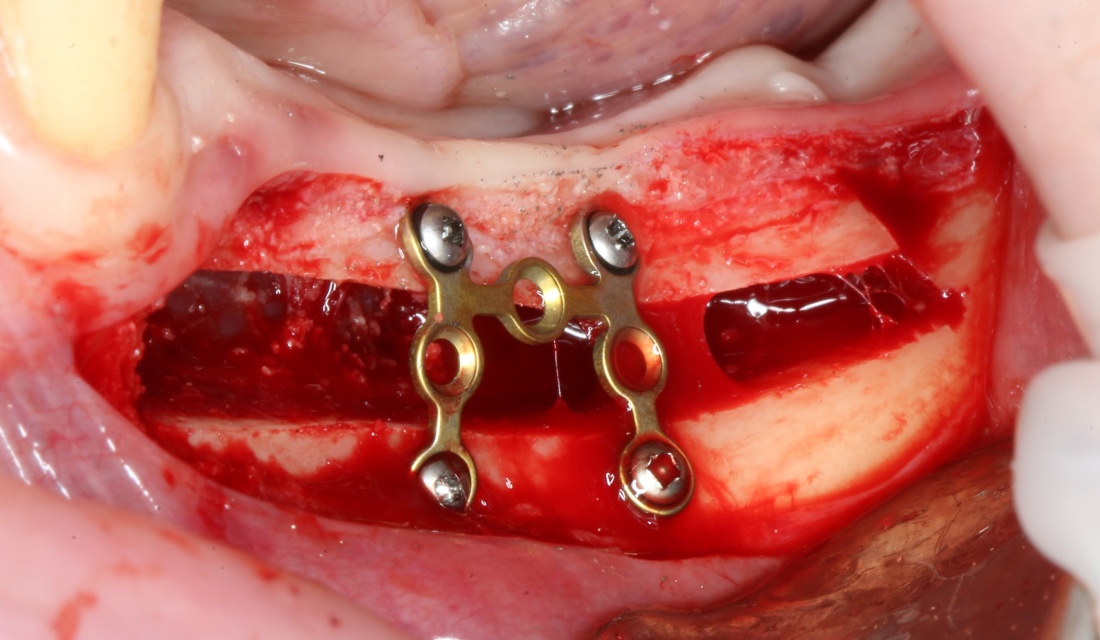

Я зафиксировал костный блок практически без адаптации на несколько винтов. Обрати внимание, что винты находятся в зоне, где не планируется установка имплантатов. Фиксация должна быть надежной, поскольку мне еще предстояла подготовка лунок для имплантатов. Трех винтов для этого вполне достаточно.

Дальнейшая адаптация костного блока свелась к сглаживанию острых краев. После чего я приступил к подготовке лунок и установке имплантатов.

Глянем на то, что получилось:

Осталось адаптировать костный блок (убрать острые края), проверить его фиксацию и, при необходимости, добавить винты. Десятисекундное дело.